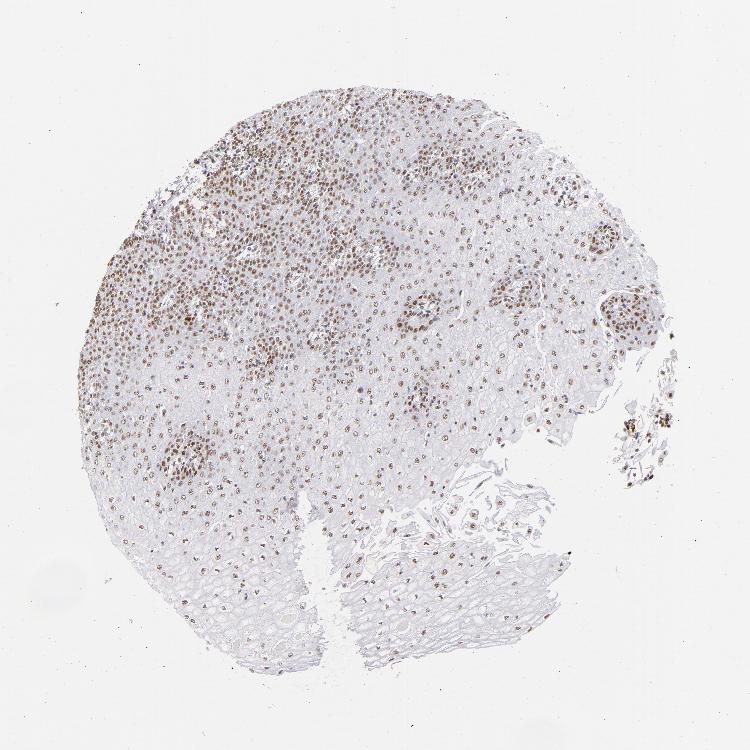

ESOPHAGUS - Antibody stainingi

Antibody staining in the annotated cell types in the current human tissue is reported as not detected, low, medium, or high, based on conventional immunohistochemistry profiling in selected tissues. This score is based on the combination of the staining intensity and fraction of stained cells.

Each image is clickable and will lead to virtual microscopy that enables deeper exploration of all samples and also displays staining intensity scores, fraction scores and subcellular localization as well as patient and tissue information for each sample.

Antibody HPA001912

Squamous epithelial cells Low